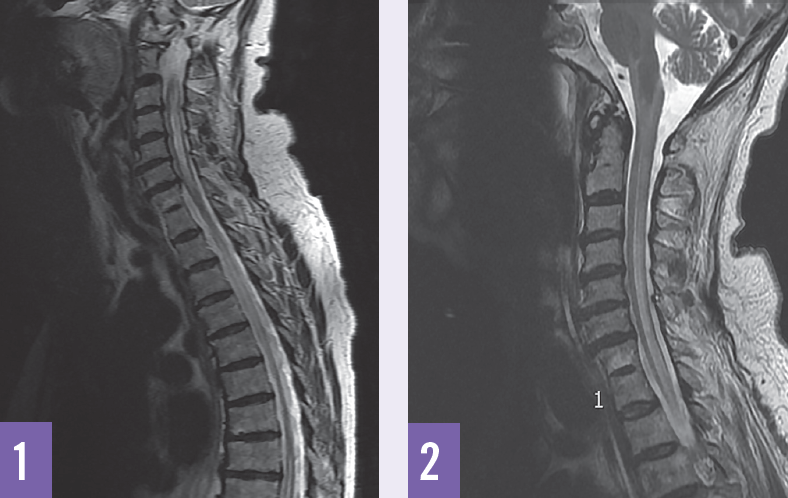

James J. Contestable, MD; Farhan I. Kashem; Sean M.S. Wade, MD

A 75-year-old woman presented to the emergency department with a 5-day history of urinary retention, lower extremity numbness, and profound lower extremity weakness.